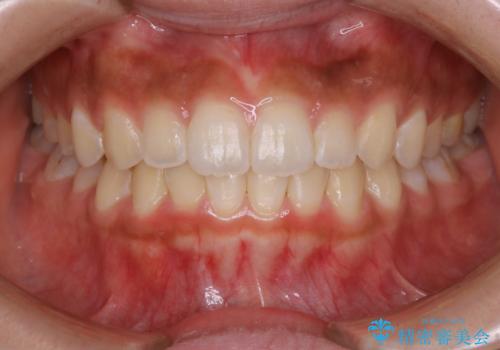

短期間ですきっ歯を改善:インビザラインLite

- 上の歯がすきっ歯なのと、歯が出ている気がするとご相談にいらした方です。

奥歯の噛み合わせに大きな問題がなく、患者様のご希望もあったため、前歯部メインで治療するインビザラインLiteで治療を行いました。

日常的に舌を突出する癖があったため、後戻り防止のために舌および口唇の筋機能訓練も合わせて行いました。

横顔のシルエットが改善し、口元もスッキリとなりました。

舌癖がある方は、歯を内側から押し出す力が日常的に働くため、矯正治療後も歯と歯の隙間が開いてしまうなどの後戻りのリスクが高いことが知られています。舌の正しいポジショニングやお口周りの筋肉のトレーニングを行うことで後戻りのリスクを減らすことが可能です。